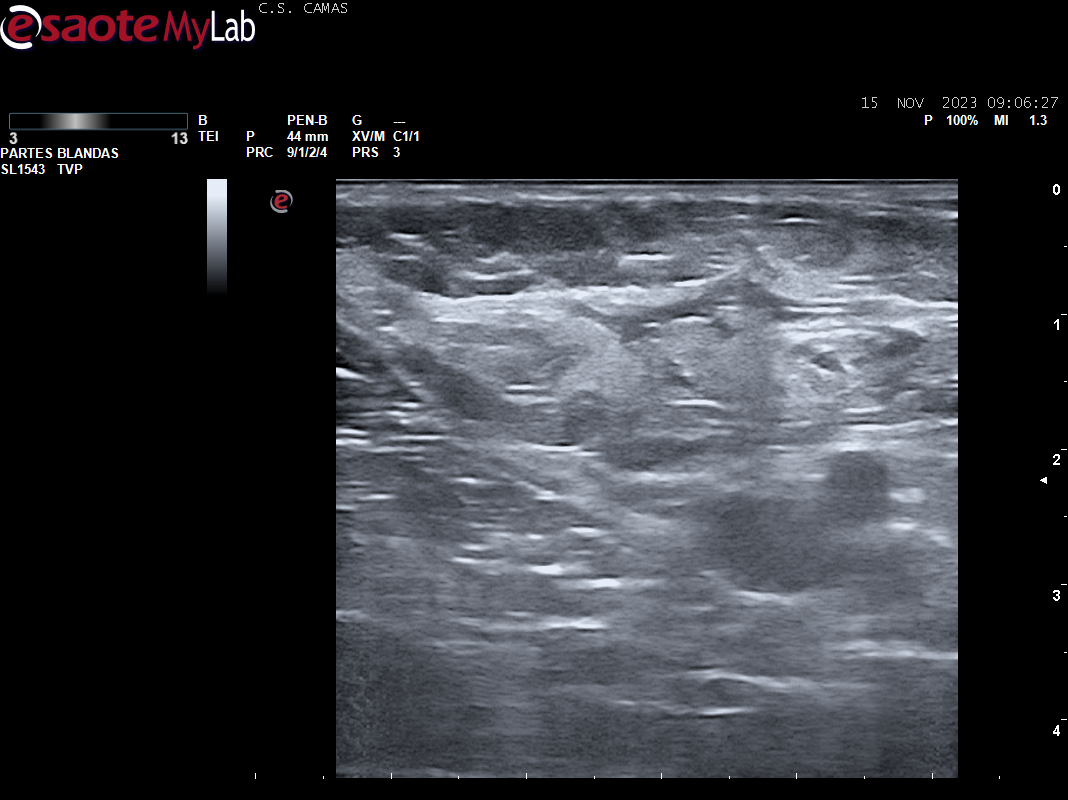

Ecografia vascular cara interna del muslo izq: Trombosis de todo el recorrido de la safena izq con dolor al paso de la sonda por colaterales inferiores que colapsan. Presenta además en zona del cayado de la safena imagen heterogenea sin apreciar la llegada de la safena a la femoral común compatible con arrancamiento de la misma.

Trombosis de todo el recorrido de la safena interna izquierda con tromboflebitis de las colaterales inferiores que concuerda con el diagnóstico hospitalario.

Pero al realizar la ecografía y encontrarnos ante la presencia de una safena interna trombosada pensamos que la intervención que se le ha practicado ha sido por escleroterapia con microespuma de polidocanol.

Dado que presentaba una cicatriz quirurgica para la realización de safenectomia, creemos que pudo producirse una complicación/dificultad para su realización y optaron por la realizacion de la técnica con microespuma, cuya evolución es la que presenta la paciente.